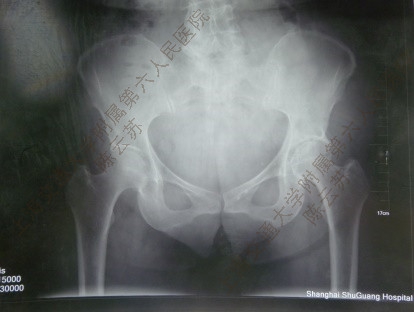

图3 术前X线片示左髋OA